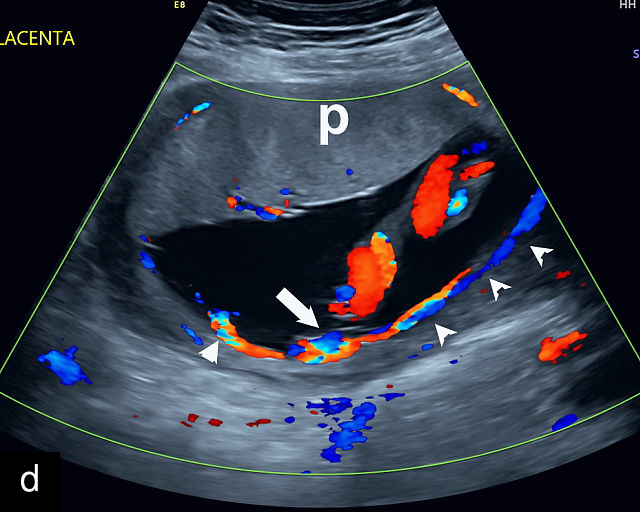

21

(a) Type-1 vasa previa. Photograph after delivery showing the umbilical cord inserting into the membranes through which unprotected fetal vessels run to insert into the placental edge. (b) Type-2 vasa previa. Photograph after delivery showing bilobed placenta with unprotected fetal vessels running though the membranes between the lobes. (c) Type-3 vasa previa in a twin pregnancy. Photograph after delivery showing unprotected vessels running through the membranes from one edge of the placenta to another (arrow). (d) Transabdominal grayscale ultrasound of the lower uterine segment showing a linear hypoechoic structure (fetal vessel) running over the cervix (c) indicating vasa previa (Type 2). b, bladder; h, fetal head. (e) Transabdominal color Doppler ultrasound of the lower uterine segment showing fetal vessels (arrow) running over the cervix (c) indicating vasa previa (Type 2). (f) Transabdominal ultrasound with color flow and pulsed-wave Doppler of the lower uterine segment showing a fetal vessel running over the cervix (c) indicating vasa previa (Type 2). Pulsed-wave Doppler demonstrates an umbilical arterial waveform. (g) Transvaginal grayscale ultrasound with showing a Type-2 vasa previa. There are two placental lobes, an anterior (a) and a posterior (p) lobe. There is a linear and circular hypoechoic structure (arrow) running over the cervix (c) between the lobes. (h) Transvaginal grayscale ultrasound image of vasa previa. A hypoechoic linear structure (arrow) is seen running through the membranes over the cervix (c). h, fetal head. (i) Transvaginal grayscale ultrasound of vasa previa. Hypoechoic circular and linear structures are seen close to the internal os. (j) Transvaginal color Doppler ultrasound image of vasa previa. A fetal vessel is seen running through the membranes over the internal os (arrow) of the cervix (c). h, fetal head. (k) Transvaginal ultrasound with color Doppler showing a Type-2 vasa previa. There are two placental lobes, an anterior and posterior lobe (pl). Fetal vessels run over the cervix between the lobes. (l) Transvaginal color flow ultrasound with pulsed-wave Doppler image of vasa previa. Color Doppler shows flow through the vessel and pulsed-wave Doppler shows a fetal umbilical venous waveform. (m) Transvaginal color ultrasound with pulsed-wave Doppler image of vasa previa. Color flow Doppler shows flow through the vessel and pulsed-wave Doppler shows a fetal umbilical arterial waveform. (n) Transvaginal three-dimensional ultrasound with color Doppler image of vasa previa. h, fetal head; c, cervix.

12

Transvaginal ultrasound imaging of Type-1 vasa previa. Color Doppler (a,c,d) and grayscale (b) imaging shows fetal vessels running over the cervix.

In all pregnancies, the placental cord insertion should be identified at the time of the second-trimester anatomy scan. In addition, a color flow Doppler sweep of the region overlying the cervix should be performed. The ultrasound appearance of vasa previa is of hypoechoic linear or circular structures overlying or in close proximity to the internal os (Figure 21).30,187,252,263 When these are observed, color flow Doppler should be employed to confirm flow through these structures.30,187 Transvaginal ultrasound with color and pulsed-wave Doppler is essential for diagnosing vasa previa; the presence of a fetal arterial or venous waveform on pulsed-wave Doppler confirms the diagnosis (Figure 21). A common misconception is that vasa previa occurs only when a fetal artery overlies the cervix; however, a fetal vein overlying the cervix also constitutes vasa previa (Figure 21l).265 The precise distance of fetal vessels from the internal os required to define vasa previa has been debated.266 While some have used a distance of 2 cm, others argue that unprotected fetal vessels within 5 cm of the internal os are at risk of rupture, particularly given that the cervix dilates to 10 cm during labor. Some experts advocate for a 5-cm threshold to define vasa previa.266,267 An international Delphi consensus of vasa previa experts recommended that the definition should not be limited to a 2 cm cutoff, acknowledging the variability in clinical practice.268

Transvaginal ultrasound with color flow Doppler is highly accurate in the diagnosis of vasa previa, with a systematic review and meta-analysis finding sensitivity and specificity of greater than 99%.269

False positives may arise due to several factors, including funic presentation (where free loops of the cord overlie the cervix), movement artifacts on color Doppler, placenta previa or maternal vessels.30,263 Free loops of the umbilical cord typically move away from the cervix with changes in maternal position and do not persist on serial ultrasound examinations.187

When vasa previa is suspected during the second trimester, transvaginal sonography with color Doppler should be repeated at around 32 weeks to confirm the diagnosis. This follow-up is essential, as 15–40% of vasa previa cases identified in the second trimester resolve spontaneously before delivery.270,271 It is also critical to ensure that the fetal head is not engaged, as this can compress and obscure fetal vessels, potentially leading to a false-negative diagnosis.272 In such cases, manual elevation of the fetal head may be necessary, but care must be taken to avoid compressing the vessels during this maneuver, as it can also result in a missed diagnosis.273